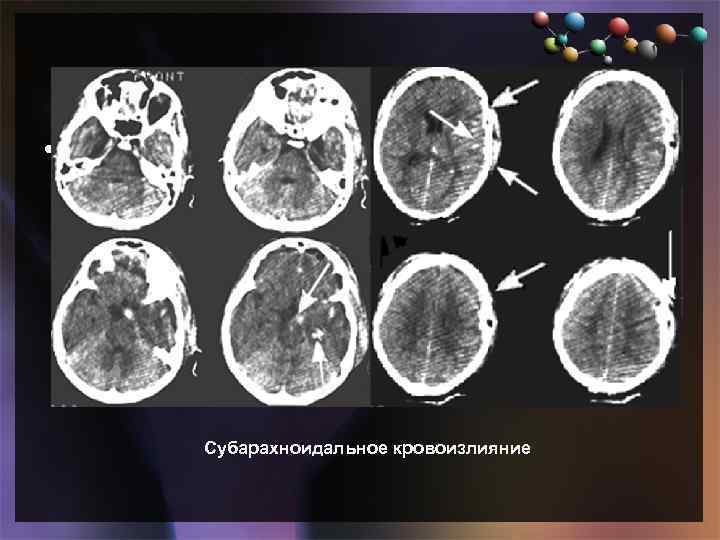

• Подзаголовок слайда Субарахноидальное кровоизлияние

• Подзаголовок слайда Субарахноидальное кровоизлияние